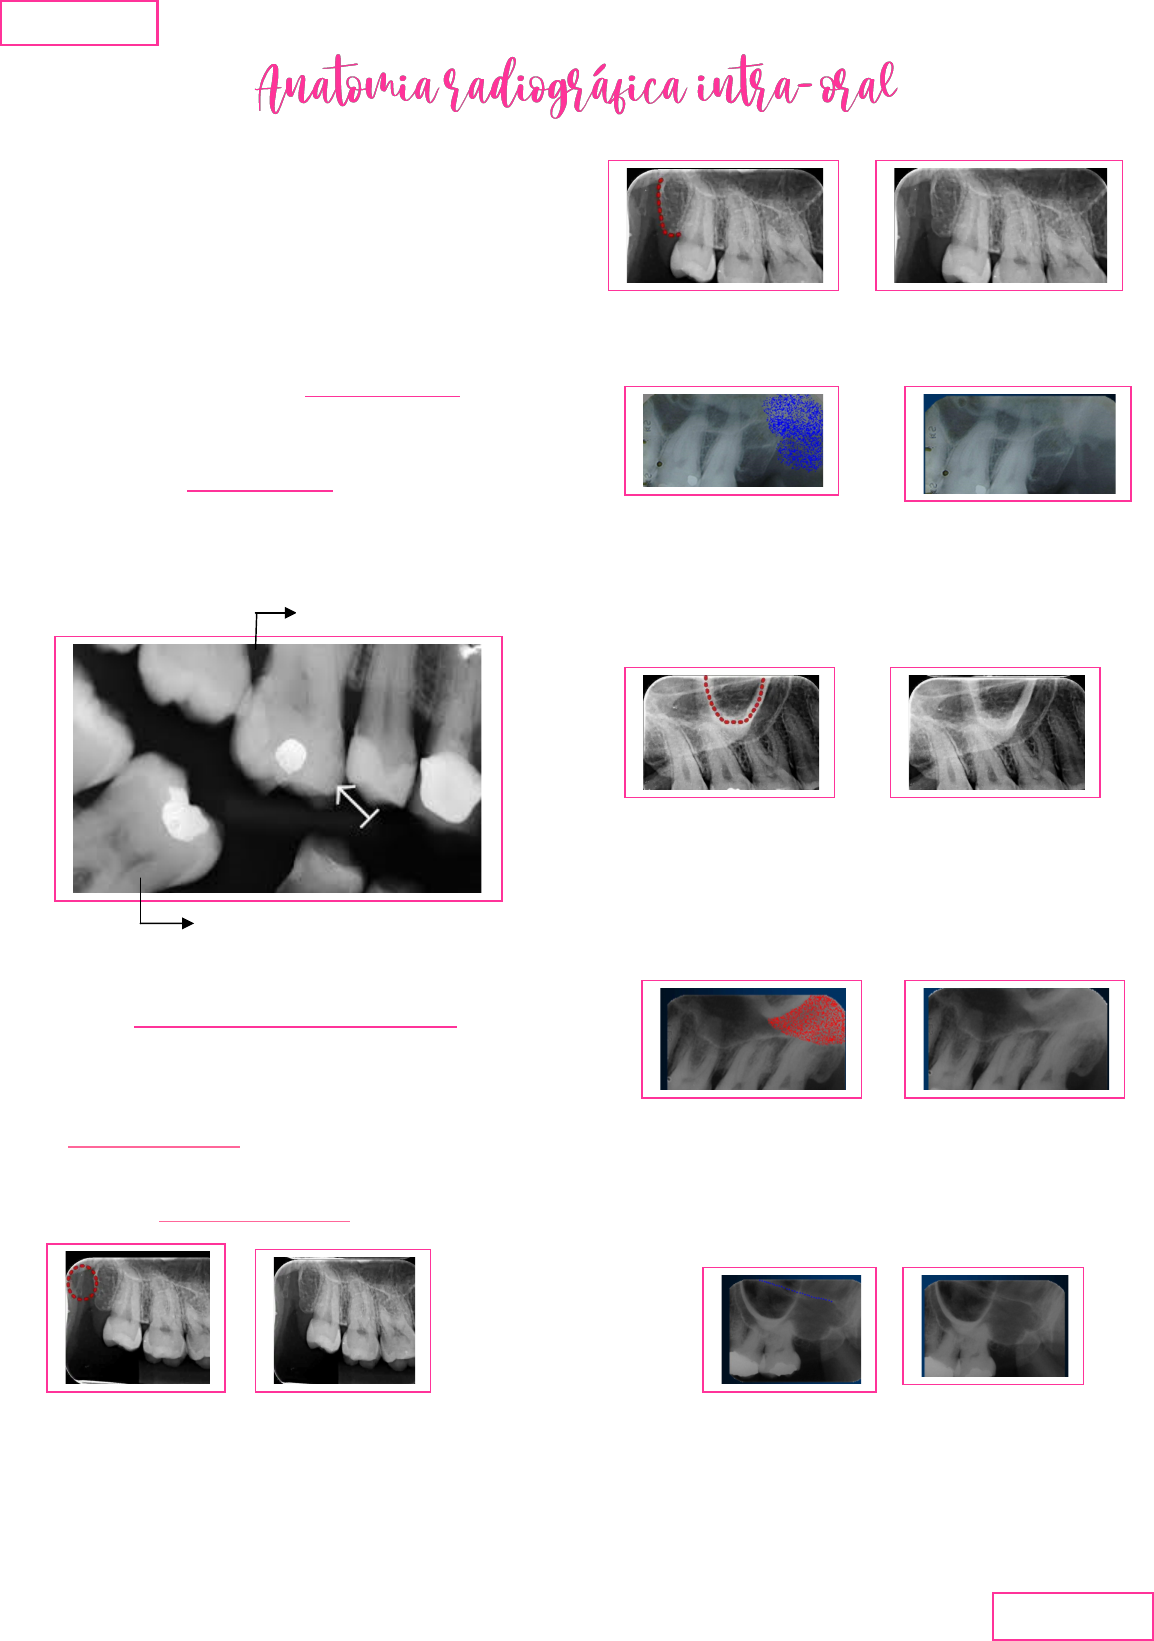

- As imagens radiográficas é um registro de

raio sombras claras e escuras (radiação

eletromagnética)

-Radiopacos: quanto mais denso, mais cálcio e

mais espessa a estrutura, ira absorver mais

radiação, formando uma imagem branca., ex:

esmalte

- Radiolucida: imagem negra, ex: polpa.

* restaurações metálicas são mais opacas,

(brancas), pois absorvem totalmente a radiação.

Estruturas da maxila:

1. Hâmulo piterigoide:

- pouco radiopaco, pois a estrutura é fina,

localizado na parte posterior quando se

radiografa molares superiores.

2. Tuberosidade da maxila:

- fica distalmente ao ultimo dente erupcionado,

aspecto de osso reticulado.

4. Processo zigomático da maxila:

- Aspecto de “u” ou “v”, sobressai o 1° e

2° molar

5. Osso zigomatico:

- Em radiografia intra-oral não consegue

visualizar o arco zigomático.

6. Soalho na fossa nasal.

- Linha reta no alto da radiografia

7. Seio maxilar

- inicia a partir de canino;

Radiopacos

Radiolucidos

-radiolucido,delimitado por uma cortical

(linha)

-extensão em direção a tuberosidade da

maxila;